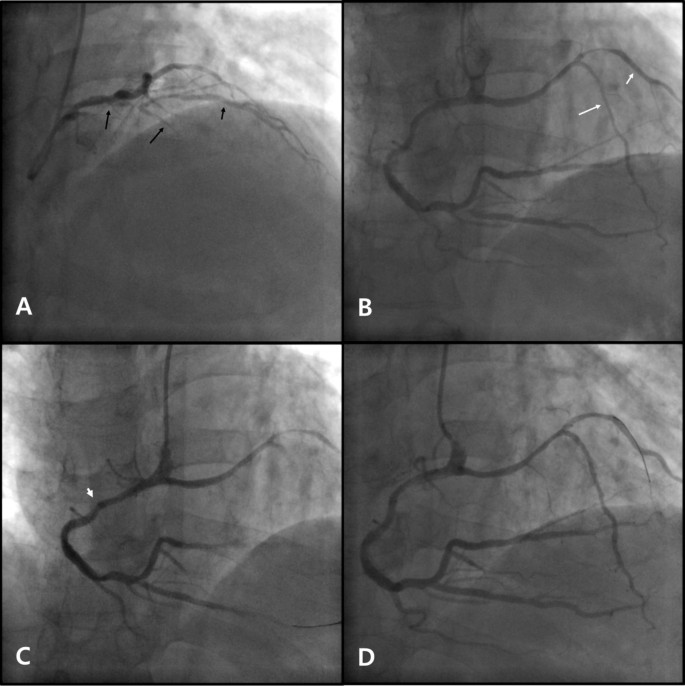

On the second day after admission, coronary angiography was performed. Left coronary angiography revealed a short LAD originating from the LMCA, giving rise to proximal septal branches and the first diagonal artery (D1) (Figure 1A). There was significant stenosis of the proximal portions of the short LAD and the D1, and there appeared to be total occlusion of the mid portion of the short LAD. The left circumflex artery originated normally from the LMCA and showed no significant stenosis. Right coronary angiography revealed a dominant RCA with a long LAD originating from its proximal portion (Figure 1B). The RCA originated above the right coronary sinus and pointed downwards. The long LAD coursed left until turning downwards to the apex, giving rise to the second diagonal artery (D2) at the turning point. No bridging phenomenon was observed in systole in the traversing portion of the long LAD. There was significant stenosis of the mid portion of the long LAD, the proximal portion of the D2, the distal RCA and the proximal portion of the posterior descending artery.

Coronary angiography and percutaneous coronary intervention. A) Short LAD (long black arrow) originating from the LMCA, giving rise to the D1 (short black arrow). There is significant stenosis in the proximal portion of the short LAD and the proximal portion of the D1. (B) Long LAD (long white arrow) originating from the proximal RCA, coursing left, then turning downwards to the apex, giving rise to the D2 (long white arrow). There is significant stenosis of the distal RCA, the proximal PDA, the mid portion of the long LAD and the proximal portion of the D2. (C) Deep engagement (arrowhead) with a 6 Fr MP guiding catheter to deliver stents to the distal RCA. (D) Balloon angioplasty with a 6 Fr JR 4.0 guiding catheter at the mid portion of the long LAD and the proximal portion of the D2. LAD, left anterior descending artery; LMCA, left main coronary artery; D1, first diagonal artery; RCA, right coronary artery; PDA, posterior descending artery; D2, second diagonal artery; 6 Fr, 6 French; MP, Multipurpose; JR, Judkins right.

PCI was performed using a right trans-radial approach with a 6-French sheath. Deep engagement with a Multipurpose (MP) guiding catheter (Cordis Corporation, Bridgewater, NJ, USA) was required to deliver a balloon and stents through the downward-oriented RCA ostium (Figure 1C). Xience Prime everolimus-eluting stents (Abbott Laboratories, Illinois, USA) were implanted in the distal RCA and the posterior descending artery (stent size 3.0 × 24 mm and 3.5 × 24 mm, respectively). Successful balloon angioplasty was performed with a Judkins right (JR) 4.0 guiding catheter (Cordis Corporation, Bridgewater, NJ, USA) and a 2.5 × 20 mm Ikazuchi balloon (Kaneka Medical Products, Nagoya, Japan) in the long LAD and the D2 (Figure 1D). The procedure was terminated at this point because of concern about the difficulty of delivering a stent through the acute angle between the proximal RCA and the traversing portion of the long LAD with poor guiding catheter support. Finally, a Judkins left 4.0 guiding catheter (Cordis Corporation, Bridgewater, NJ, USA) was used in the short LAD and a 3.0 × 28 mm Xience Prime stent was implanted in the short LAD, crossing over the D1.

Unlike the previous case, our patient underwent PCI. Although the MP and the JR 4.0 guiding catheters were suitable for coaxial positioning with the downward-pointing RCA and the traversing portion of the long LAD, they did not provide good support. Deep intubation as used in this case is one way to improve the backup force in transradial interventions [8]. Alternatively, a buddy wire technique, buddy balloon technique, different choice of guiding catheter, or transfemoral approach could improve support [9, 10].